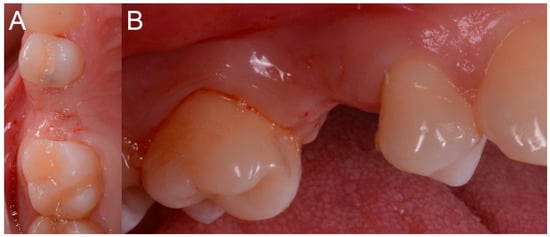

The patient sat on the dental chair (Figure 6) and rinsed 3 or 4 time with chlorexidine 0.2% mouthwash, 10 min before surgery, for a total of 2 min.

Figure 6.

Pre-operative situation. (A) Occlusal view. (B) Lateral view.

After local anesthesia by infiltration with articaine with adrenaline (at a ratio of 1:100,000) the surgeon positioned the dental-supported surgical guide, verifying its stability and the exact adaptation on the occlusal surfaces of the teeth (Figure 7).

The implant was initially inserted through the handpiece, set with a maximum insertion torque of 30 Ncm; exceeding this threshold, the surgeon proceeded manually for better control. At the end of the insertion, the surgeon proceeded to remove the template and check the implant axis with a dedicated instrument, then placed a transmucosal healing screw of such height as not to be covered by mucosa during the healing phase (Figure 10).

Figure 10.

Post-surgical rx control of the implant and healing abutment.

The operation was completed and the patient was left to go home with the indication to perform 3 or 4 mouthwashings with chlorexidine 0.2% within 4 days after the operation, and with a prescription of painkiller to be taken when needed (ibuprofen 600 mg, maximum 2/day). Since no sutures were placed, the first follow-up visit was set at 10 days after the intervention.